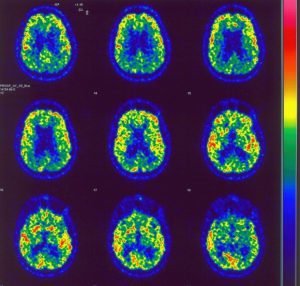

Enfermedades Cerebrales

Información sobre enfermedades cerebrales desarrollada por los profesionales especializados en neurorrehabilitación de Irenea, Instituto de Rehabilitación Neurológica de Vithas